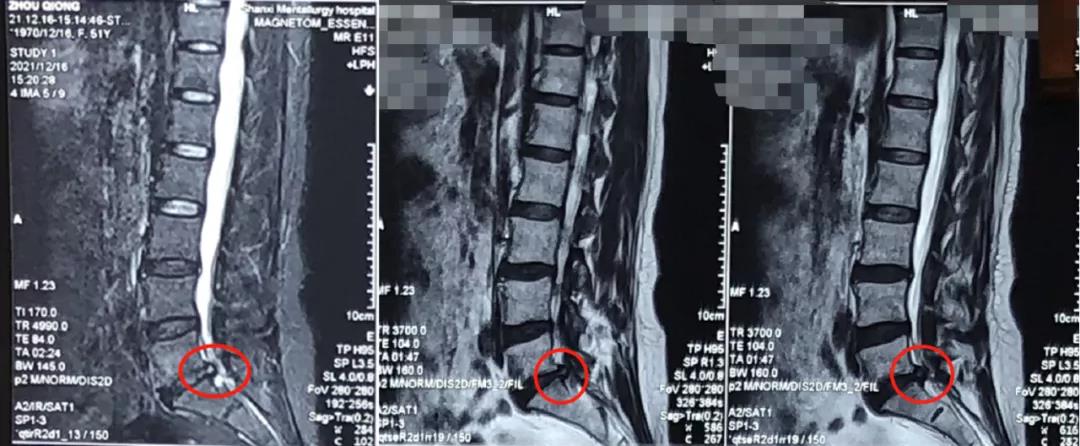

熊东主任接诊后,结合赵女士的查体及其他各项检查结果,确诊患者为“腰椎间盘突出症(腰5骶1)”。从患者的影像学资料可以看到,在腰5骶1处已经出现比较严重的突出并且压迫到神经,患者的症状明显,这种情况建议进行椎间孔镜手术微创治疗。

术前影像学资料: